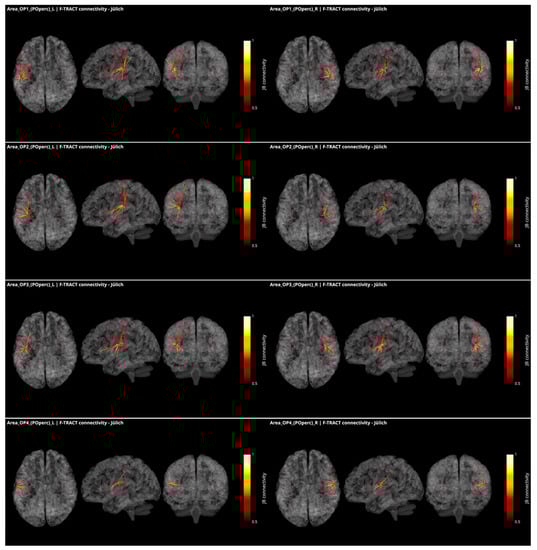

These responses to brief electrical pulses mimic the physiological propagation of signals along axonal populations and manifest as modulations of cortical activity in the connected regions. After stimulation artifact correction [], the first CCEP component is considered to reflect direct connectivity with the stimulated region. The investigations using this methodology are able to demonstrate causal interactions between brain areas in vivo, known as effective connectivity []. To infer reliable connectivity information however, large amounts of data are required, which is what the multicenter F-TRACT initiative strives to do. Ultimately, the goal of the F-TRACT project is to provide a large-scale functional atlas for each region of the main brain parcellations, at different resolution scales (https://f-tract.eu, version 1 December 2021). Using our latest internal version of the F-TRACT atlas including a total of 942 implantations, we examined connectivity patterns from the posterior operculum (OP1, OP2, OP3 and OP4) and two insular regions (Ig1 and Ig2) presenting borders with OpP and auditory areas, as defined in the Jülich atlas of brain parcellations. Stimulation contacts belonging to the same parcellation region were pooled together and their responses, binarized by statistical thresholding with z-score threshold = 5, were used to yield a connectivity probability (for details see [,]). Thresholding was performed by excluding regions where less than five stimulations were performed, or where recordings originated from fewer than five different subjects. Thus, a square matrix of connectivity was generated, representing the probability that a response be detected in one region, when stimulating from another.

In Figure 3, all connections of the parietal operculum subregions are displayed as red dots, with the radius varying with connectivity strength. The lines represent the connections that survive the thresholding, and the colormap is set to represent connectivity values. The probability matrices are not symmetrical due to afferent and efferent connections: this is considered by modulating the coloring of the connection if the nodes at the extremities of an edge have different values in the connectivity matrix. This represents the causal relationships between regions. It appears that parietal opercular subregions (OP1-OP4) are strongly inter-connected. They are also connected by efferences with frontal opercular subregions and with granular and dysgranular subcomponents of the insula within the same hemisphere. In addition, left and right OP1, OP2 and OP3, but not OP4, present efferent connectivity with somatosensory cortex ipsilaterally. Interestingly, connections from the OP1, OP2 and OP3 subregions to the temporal auditory regions of the superior temporal gyrus (TE1, TE2.1, TE2.2) were only found in the right hemisphere and only OP2 in the left one. Connections to subregions of the Heschl gyrus were found from OP1, OP2 and OP4 in the right hemisphere and from OP2 in the left hemisphere. This asymmetry between right and left hemisphere could be related to the asymmetry of the auditory cortex with left hemisphere more sensitive to speech and right hemisphere to melodic contents []. Other efferences from all OpP subregions were found to inferior parietal lobule and from bilateral OP1 and OP3 to frontal area 44. No interhemispheric connectivity was reported here probably because the CCEP amplitude decays with distance and thus the chance of observing an existing connection decreases with the distance between regions. However, lowering the probability threshold permitted to find connectivity with homotopic regions of the opposite hemisphere. Notably no connections with the limbic system could be observed. To summarize the connections from OpP to both auditory and somatosensory cortices, only right OP1, bilateral OP2 and right OP3 were evidenced, providing potential somatosensory–auditory integration properties to those regions.

Figure 3.

Intracortical connectivity of the four subregions of the parietal operculum from Jülich (‘JB connectivity’ stands for Jülich Brain connectivity). From top to bottom: area OP1, area OP2, area OP3 and area OP4. Left column for the subregions of the left hemisphere and right column for the subregions of the right hemisphere. Image derived from the data of the F-TRACT project (https://f-tract.eu), version of 1 December 2021.

CCEP in the human operculum has been published based on the data acquired in 31 patients []. The data of this group and others are collected in the database of the F-TRACT project. Here, only the connectivity from a given region that survives strict thresholding (at least 10 stimulations from at least 5 patients) are further considered, which may explain why some results described by these authors were not reproduced here. The fact that all the red dots, including some with probability close to 1, are not connected also reflects the strict thresholding applied in the process.